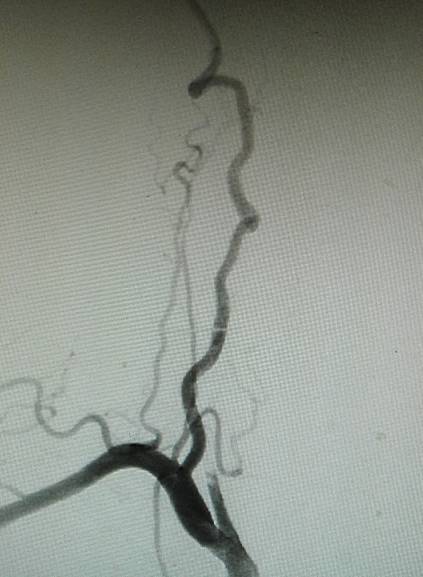

术前造影:右侧颈总动脉起始部显影,其余部位闭塞。颈外动脉向颈内动脉代偿供血。

经动脉鞘造影,可见颈总动脉通畅,但管腔狭窄,不规则。

然后球囊扩张,植入颈总动脉支架,造影示,右侧颈总动脉显影好。